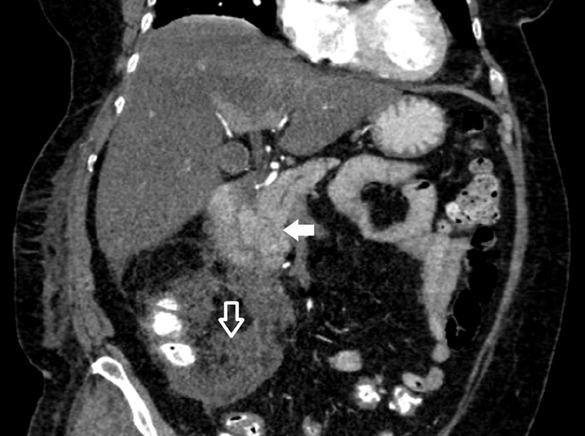

Abstract Image